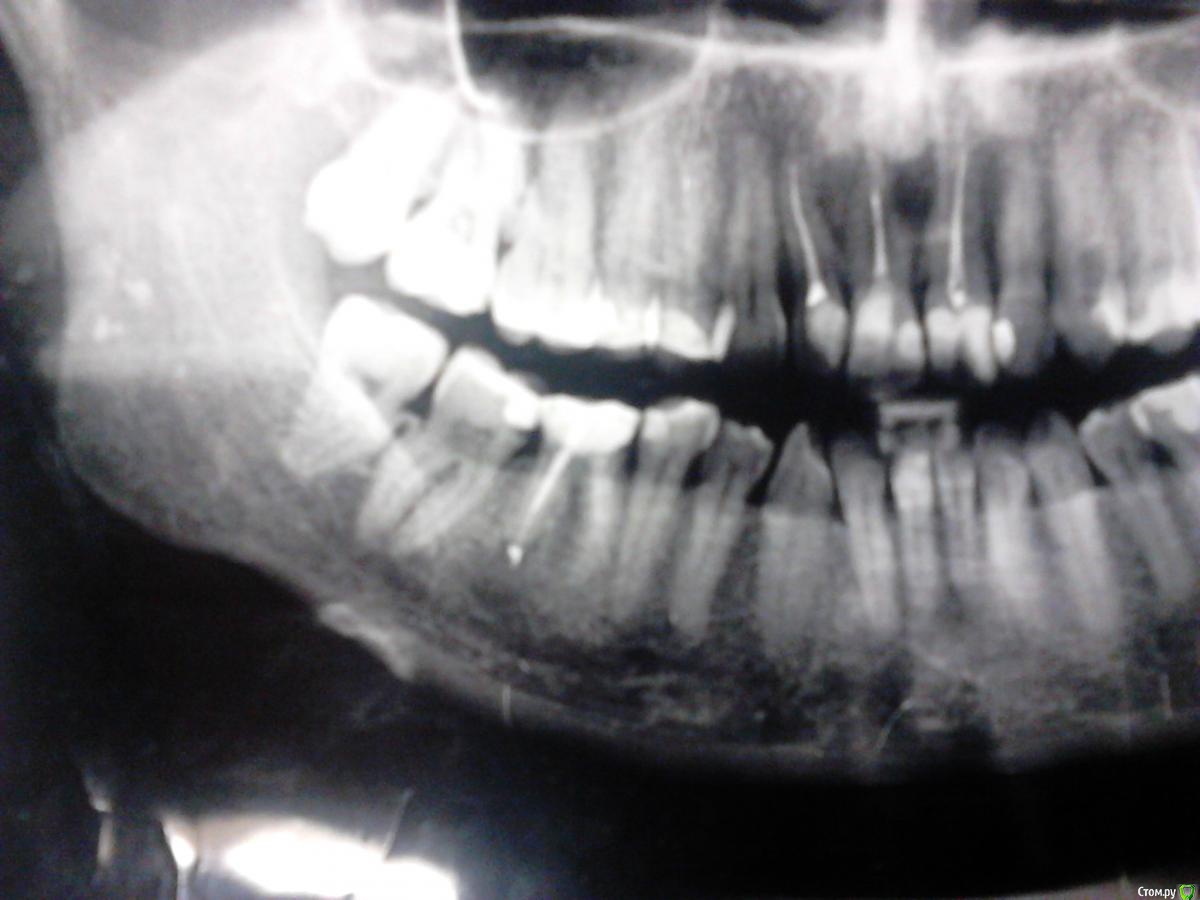

Фотина Опубликовано 13 декабря, 2016 Автор Поделиться Опубликовано 13 декабря, 2016 https://yadi.sk/d/pxAOg2f-33PmD4 Это все КТ. https://yadi.sk/d/-B6PgdUP33Pm4R Только одна папка. КТ свежее, а панорамный снимок 2015 г. С 46 тоже надо что-то делать. Перепломбировка каналов (более 2 лет назад) не принесла положительных результатов: киста осталась ((( Ссылка на комментарий

IvanK Опубликовано 13 декабря, 2016 Поделиться Опубликовано 13 декабря, 2016 исходя из картины, которую Вы показали:консультация ортодонтаповторное лечение 12,11,21, 46, с последующим протезированиемлечение 47... Ссылка на комментарий

Фотина Опубликовано 13 декабря, 2016 Автор Поделиться Опубликовано 13 декабря, 2016 Извините, речь конечно же о 47 и 46 зубах. Ссылка на комментарий